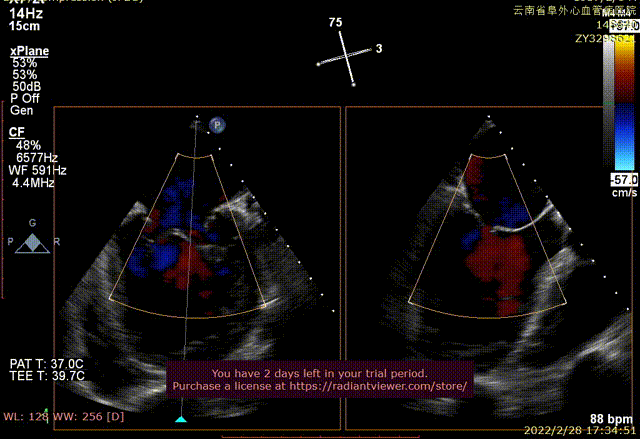

术前xPlane view提示:二尖瓣重度反流

术后xPlane view提示:二尖瓣反流显著减少